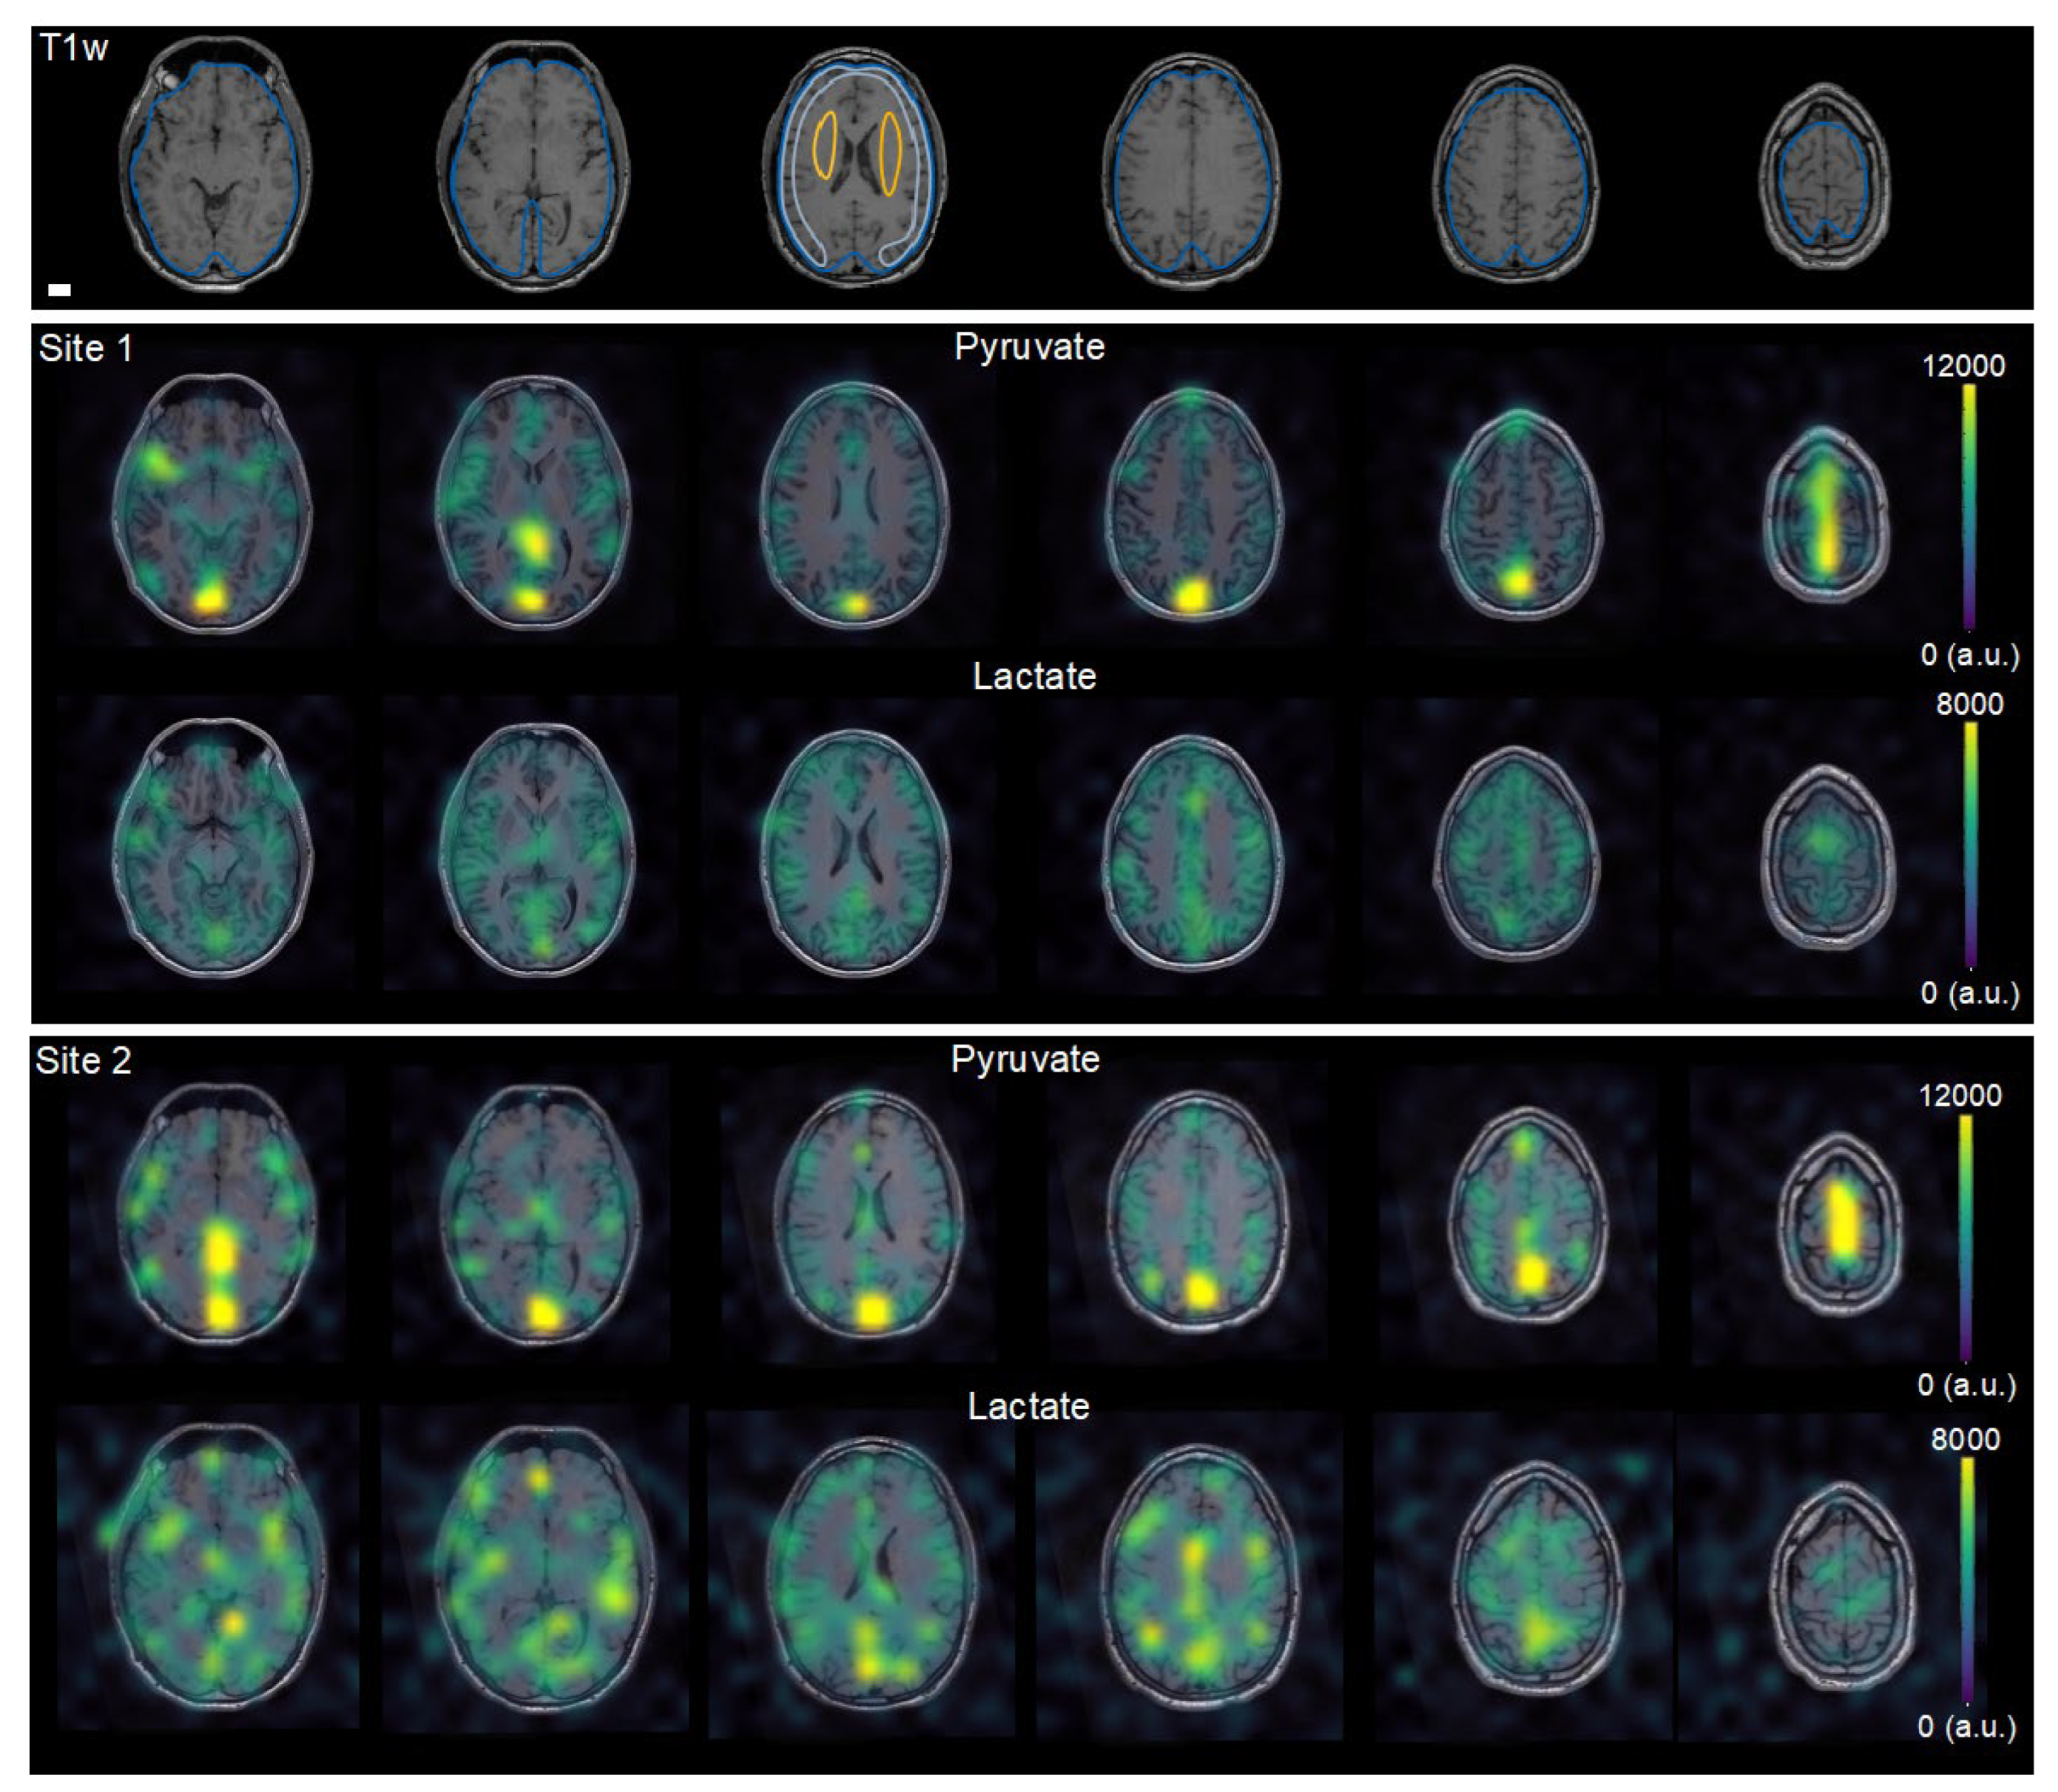

| Protocol | Site | Excitation | Flip-Angles, Pyruvate/ Metabolites | Read Out | TR/TE (ms) | Voxel Size †, Pyruvate/ Metabolites (mm3) | Temporal Resolution (s) | Coil | N |

|---|---|---|---|---|---|---|---|---|---|

| 1 | 1 + 2 | Spectral-spatial | 10°/40° * | EPI | 62.5/ 21.7 | 15 × 15 × 15/ 15 × 15 × 15 | 3 | Birdcage volume | 8 |

| 2 | 1 | Spectral-spatial | 20°/30° | EPI | 125/ 30.7 | 7.5 × 7.5 × 15/ 15 × 15 × 15 | 3 | Birdcage transmit + 24-ch receive | 4 |

| Site 1 | Site 2 | |||||

| kPL | Lactate/ Pyruvate | Lactate Z-Score | kPL | Lactate/ Pyruvate | Lactate Z-Score | |

| Whole brain | 0.024 ± 0.0018 | 0.67 ± 0.17 | - | 0.024 ± 0.0021 | 0.63 ± 0.2 | - |

| Cortex | 0.025 ± 0.0019 | 0.75 ± 0.16 | −0.5 ± 1.63 | 0.026 ± 0.0013 | 0.73 ± 0.32 | −1.66 ± 1.72 |

| Deep white matter | 0.029 ± 0.0033 | 0.96 ± 0.22 | 1.56 ± 1.5 | 0.028 ± 0.0016 | 0.96 ± 0.23 | 0.95 ± 1.4 |